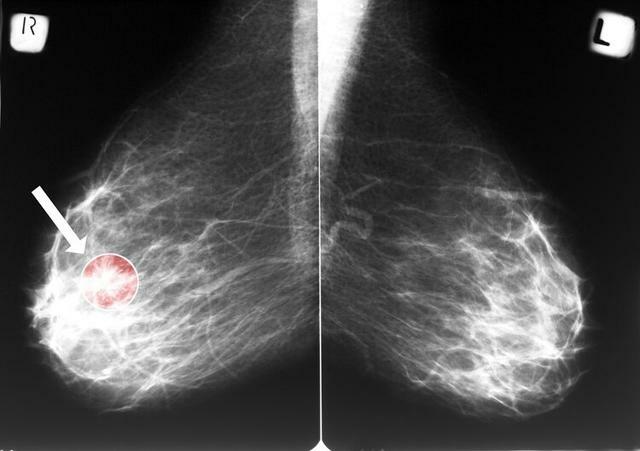

劉女士是世人眼中的成功人士,早早實現了財務自由,和丈夫感情很好,且育有一子。平靜的生活被一次意外打破,兩個月前單位組織的體檢中,劉女士被發現乳房內存在5mm的結節,病理結果顯示為乳腺癌。

得到確診癌症的消息後劉女士的心態幾乎崩了,平常沒有任何不適的她怎麼會得癌呢?好在癌症發現的早,沒有發生轉移和浸潤。

三、查出乳腺結節,離乳腺癌有多遠?

乳腺結節在臨床上十分高發,每2個女性中就有1個存在乳腺結節,這種結節一般會隨著女性體內雌激素變化而出現,是正常的生理表現。

乳腺結節更多時候是影像學上的一個特徵,並非臨床診斷。

女性需要學會看報告對於結節的診斷,一般會將其分成0~6級。

- 對於1~3級的結節,一般定期複查即可,惡變的可能性很小;

- 4~5級的結節,則需要進行穿刺、手術病理檢查明確結節的性質,再決定下一步是否進行治療;

- 6級則基本可以確定為癌症,要儘早進行治療。

建議女性從40歲開始定期進行乳腺篩查,一般是進行乳腺彩超+鉬靶檢查,具體的檢查方案還是要諮詢專業醫生。一些有條件的女性,在40歲以下也可以每年進行一次超聲檢查。